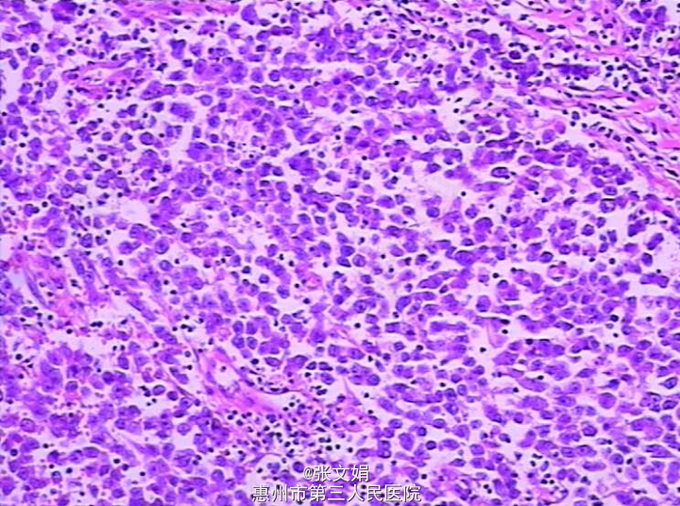

查体:左侧阴囊肿大,无疼痛。大小约为3cm*2cm大,类圆形,边缘稍规整。其余无特殊。 辅查:门诊CT检查,考虑左侧睾丸恶性肿瘤可能性大。 PET示:左侧睾丸恶性肿瘤(生殖细胞瘤)可能性,右侧斜裂小结节,考虑肉芽肿。 术后病理提示:(左侧睾丸)精原细胞瘤。

诊断:左侧睾丸精原细胞瘤 处理:行左侧睾丸根治性切除术

随访:依托泊苷针、奈达铂针 、博莱霉素针(进)化疗4程,复查CT后,未发现转移和复发。 讨论:任何睾丸肿瘤应先行高位睾丸摘除术,然后根据病理类型和临床分期选择治疗方案。精原细胞高度放射敏感,较低剂量就能消灭转移病灶而不产生明显的放射损伤。